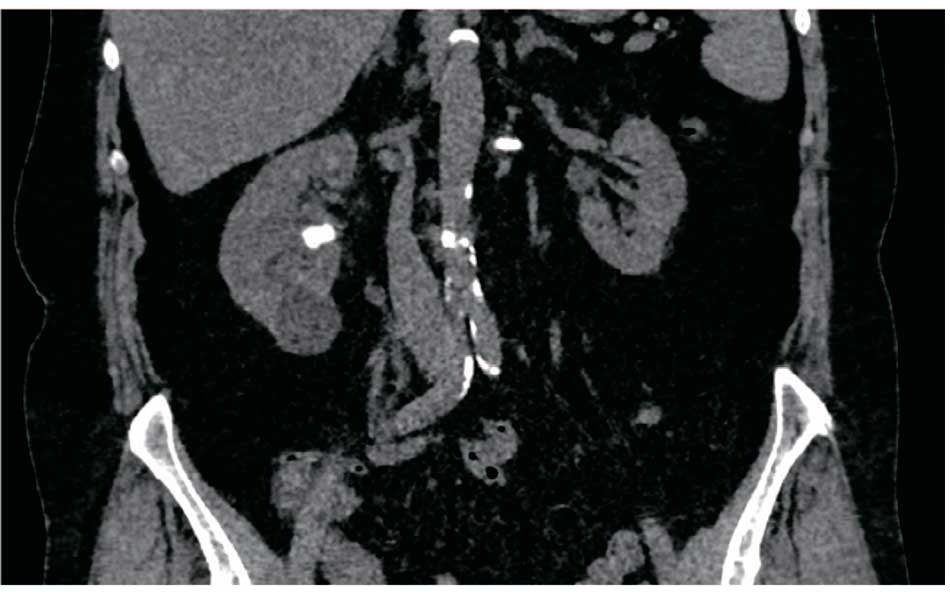

Пациентка И. 68 лет. Диагноз: Коралловидные камни обеих почек. Госпитализирована с жалобами на периодическое повышение температуры тела до фебрильных цифр. По данным КТ от 04.08.2021 г.: в чашечках и лоханке правой почки коралловидный камень (К2) размером 31х34 мм, плотностью 380 HU. В чашечках и лоханке правой почки коралловидный камень (К3) размером 32х28 мм, плотностью 450 HU. Двусторонняя пиелокаликоэктазия (рис. 6).

Рис. 6. Пациентка И. КТ почек от 04.08.2021,3D-модель, фронтальная проекция: до операции

Учитывая наличие лихорадки и двусторонней пиелоэктазии, первым этапом лечения пациентке выполнена двусторонняя нефростомия. Через 2 недели антибактериальной терапии, назначенной с учетом результатов посева мочи, полученной при пункции чашечно-лоханочной системы почек при установке нефростом, выполнены ПНЛТ справа и стентирование левого мочеточника. В послеоперационном периоде нефростомические дренажи с обеих сторон были удалены (рис. 7).

Рис. 7. Пациентка И. КТ почек: состояние после ПНЛТ справа и стентирования левого мочеточника